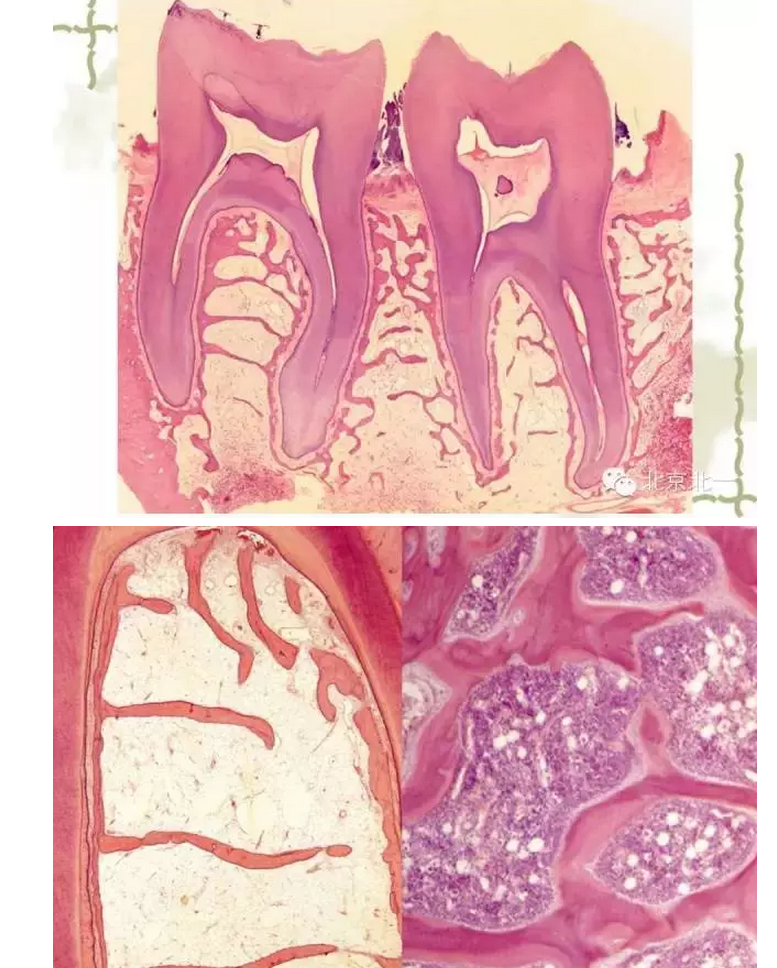

【牙周學(xué)習(xí)】牙周組織--基礎(chǔ)知識篇(下)